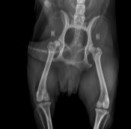

Badaniem można stwierdzić bolesność podczas biernych ruchów w stawie, mniejszy zakres ruchu w stawie, fenomen Ortolaniego – charakterystyczne „klikniecie” w stawie biodrowym wynikające z jego niestabilności. Najdokładniejszym badaniem jest badanie radiologiczne stawów biodrowych. Zdjęcie wykonuję się w projekcji grzbietowo-brzusznej – V-D, pies leży na grzbiecie (niekiedy konieczne jest wykonanie dodatkowych zdjęć w innych projekcjach). W większości przypadków do wykonania takiego zdjęcia konieczne jest uspokojenie pacjenta – sedacja i rozluźnienie mięśni – miorelaksacja, co uzyskuję się za pomocą iniekcyjnych środków farmakologicznych.

Objawy radiologiczne są różne w zależności od stopnia nasilenia zmian w stawie, dotyczyć mogą panewki stawu biodrowego, główki kości udowej lub obu struktur jednocześnie.

Do określenia stopnia dysplazji stosuje się następującą skalę ocen:

A - stawy biodrowe normalne

B - Stawy biodrowe prawie normalne

C - dysplazja nieznaczna

D - dysplazja częściowa (ograniczona)

E - dysplazja ciężka